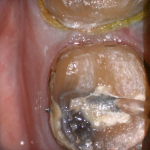

For our advanced users who mill in house or what to speed up their digital impressions we advocate taking advantage of digital dentistry’s unique features that allow you to take impressions over a period of time and segments, building larger models over different sequences and time. In this particular case we have two molars in the lower left quadrant that warranted replacement. The traditional method would be to prep both, isolate both, retract both, and take your final impression, but we will approach this as if there are two separate patients involved

For the second molar, we will take advantage of the anesthesia time and capture the first bite, the opposing, the pre-existing situation and then crop out the preparation area digitally. Once the tooth is prepared, we will check for proper reduction. We will then take the second bite to verify the vertical dimension has not changed.